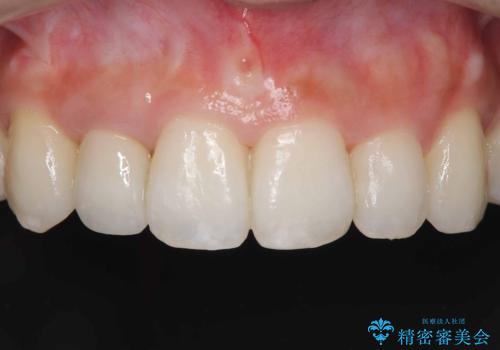

オールセラミッククラウンで治療を行いました。

歯と被せ物の境を歯肉縁下0.5㎜に設定して形成を行いオールセラミッククラウン(スペシャル)で治療を行いました。